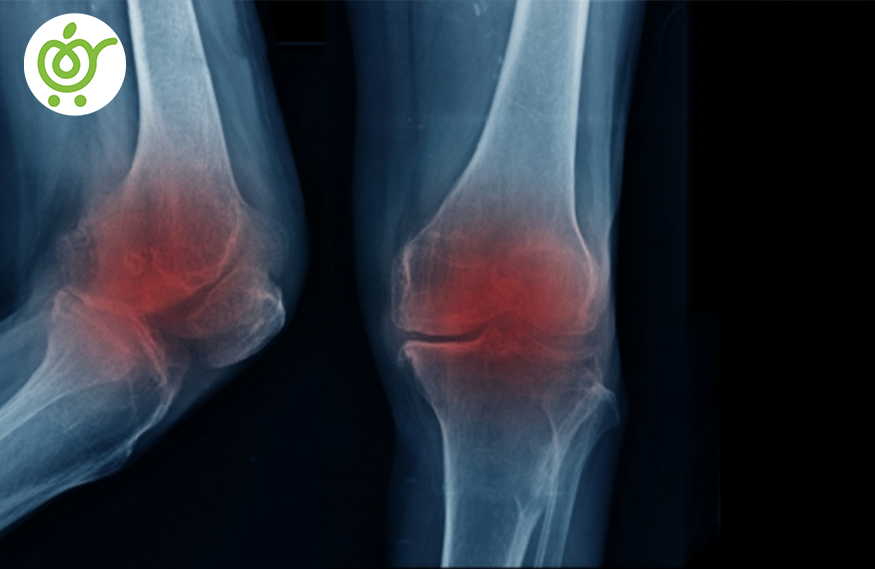

آرتروز زانو یک نوع از بیماری های مفصلی است که با تخریب زانو و سطوح غضروفی آن همراه است. این بیماری معمولاً با پیری و سن بالاتر شروع میشود، اما ممکن است در افراد جوانتر نیز رخ دهد، بهویژه اگر آنها تحمل استرس زیادی را بر زانوها داشته باشند یا از آسیبهای مکرر مفاصل رنج ببرند. در آرتروز زانو، غضروفهایی که سطح استخوانها را پوشانده و به عنوان روان کننده عمل کند، بهطور تدریجی خراب و تخریب میشوند. این باعث میشود که استخوانها بهطور مستقیم به یکدیگر برخورد کنند و باعث درد، التهاب، سفتی و کاهش حرکتی زانو شود. علایم آرتروز زانو میتواند شامل درد، سفتی، تورم، خستگی زودرس، و کاهش حرکت و انعطاف زانو باشد. اما درمانهای متنوعی وجود دارد که میتواند این علایم را کنترل کند، از جمله تغییرات در سبک زندگی، فیزیوتراپی، داروها، و در صورت لزوم جراحی نیازمند است.. اگر احساس میکنید که ممکن است زانوی شما مبتلا به آرتروز باشد، بهتر است که به پزشک مراجعه کرده و نظر و راهنمایی او را درباره تشخیص و درمان مناسب بپرسید.